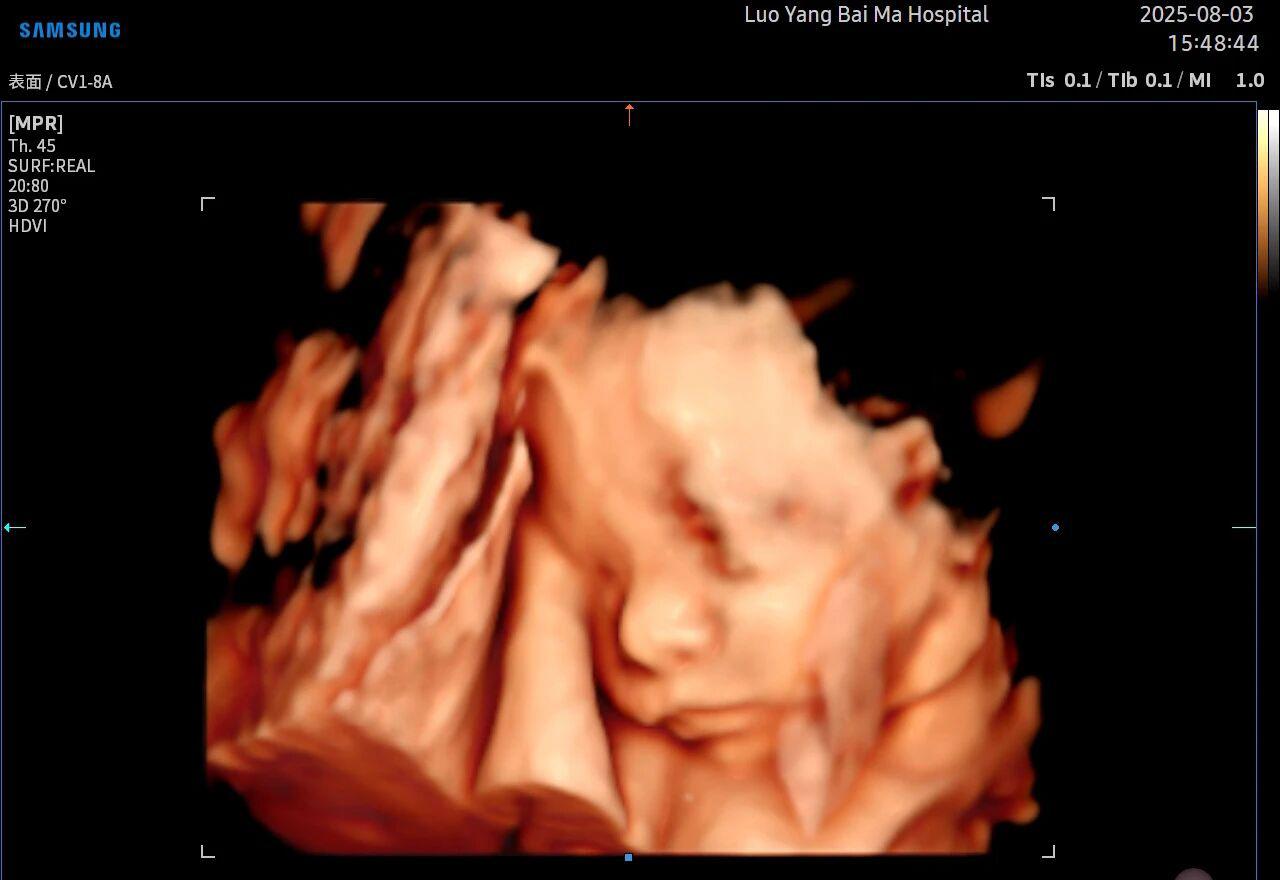

5D智能彩超拥有更高的分辨率和更强的图像处理能力,能够呈现出接近“IMAX电影画质”的细腻影像 。它采用一种被称为“水晶成像”的技术,能够穿透组织,将胎儿的骨骼、器官和组织结构以极其清晰、立体的形态展示出来。这种高清晰度对于观察胎儿微小的解剖结构细节至关重要,例如手指、脚趾、耳廓形态等,有助于医生发现一些在传统超声下不易察觉的细微异常,为排畸诊断提供了更丰富的视觉信息。

4. 温情互动,一次充满感动的“亲子会面”

除了严谨的医学诊断价值,5D彩超也为准爸妈们带来了无与伦比的情感体验。通过高清逼真的动态影像,您可以清晰地看到宝宝的每一个细微表情和动作,仿佛他(她)就在眼前。这份提前到来的“亲密接触”,不仅能极大地缓解孕期的焦虑,更能加深家庭成员与未出世宝宝之间的情感连接,让等待的每一天都充满更具体的幸福感。